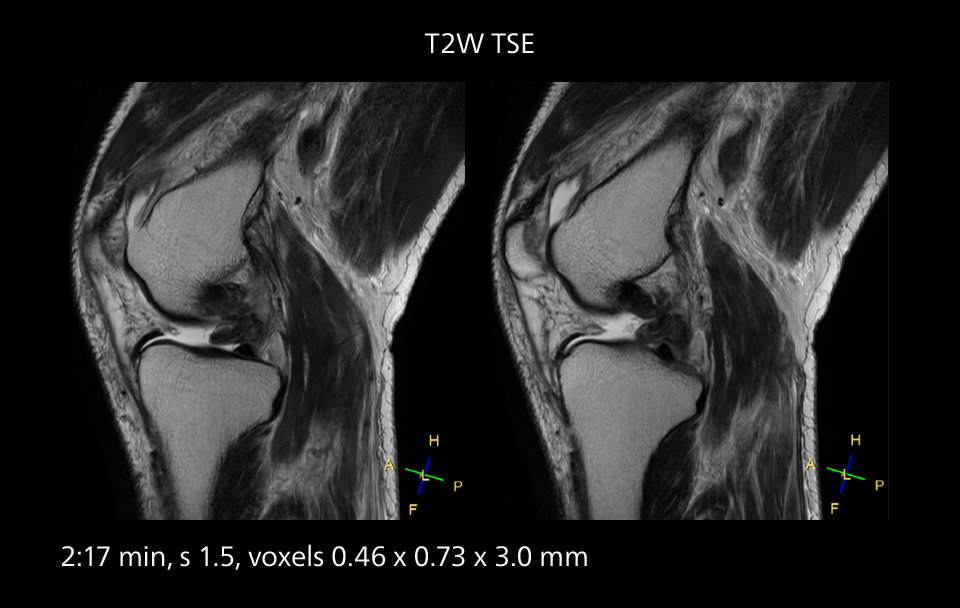

Crisp images are obtained with high resolution and short scan times using Elition X. A cyst can be seen.